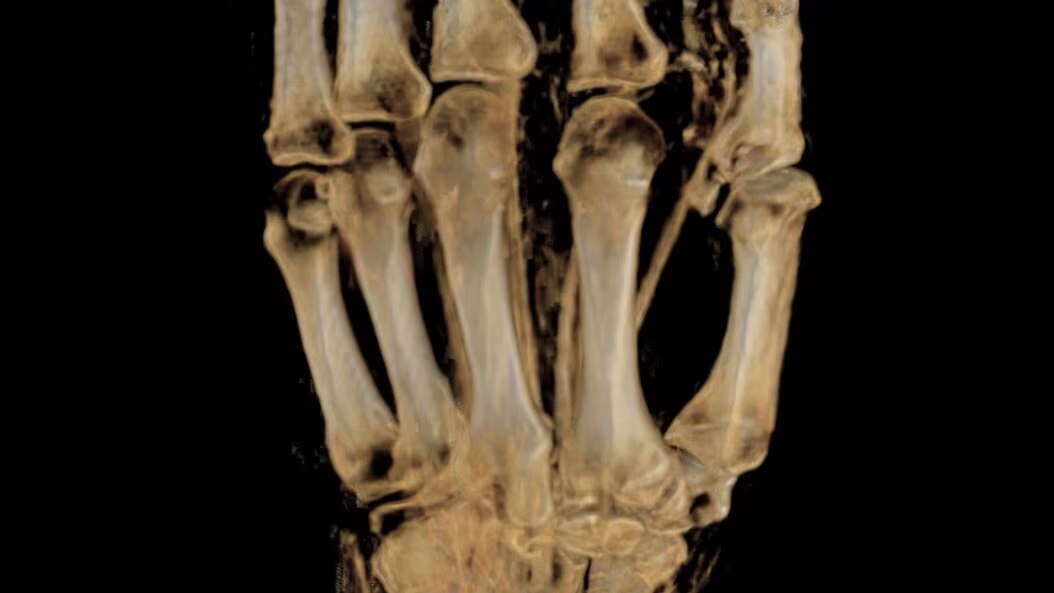

MSK MRI for SIGNA

Achieve exceptional images of bones, joints, and soft tissue with remarkable tissue contrast with MSK MRI for SIGNA. Discover the wide range of msk imaging applications now.